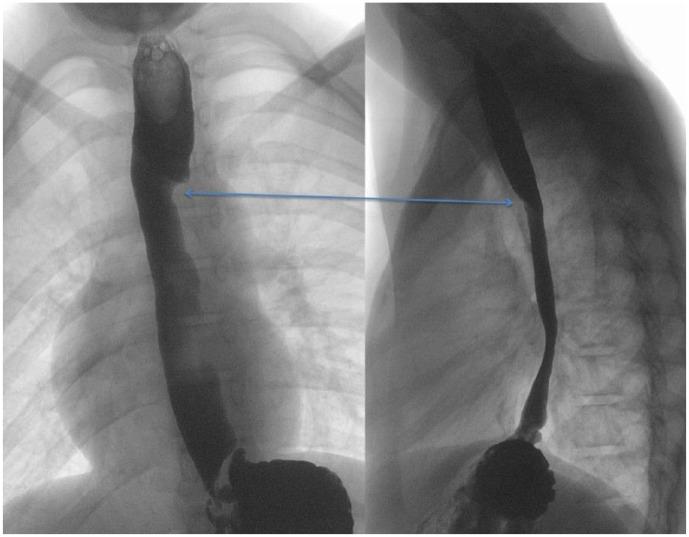

Retrotracheal Aberrant Right Subclavian Artery: Congenital Anomaly or Postsurgical Complication?

https://cdn.ncbi.nlm.nih.gov/pmc/blobs/b9ba/5846904/2f1a32a2edb1/10.1177_2333794X18762689-fig1.jpg